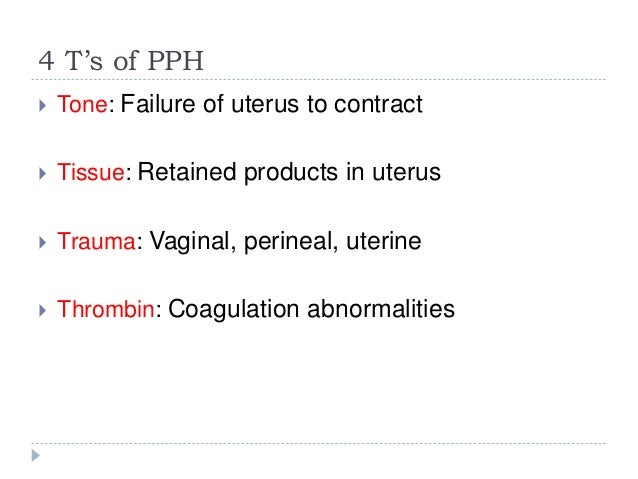

Retained placental fragments lactation free#